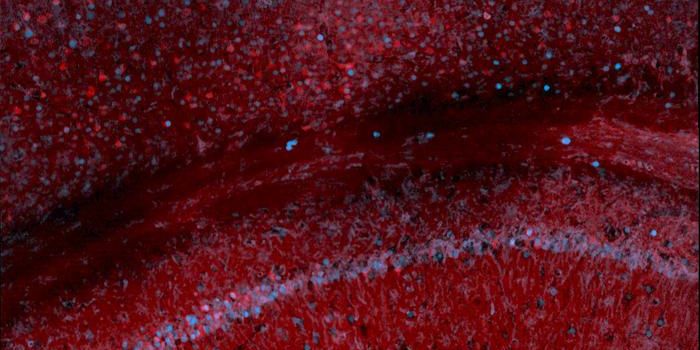

OCT 17, 2023Clinical & Molecular DXIn this photo, courtesy UC San Diego Health Sciences, regenerating neurons (yellow) can be seen along with non-regenerat ...